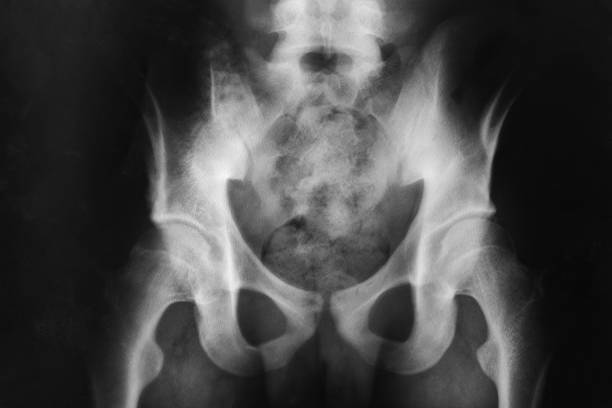

골반은 복부 하단에 위치하고 있는데 양쪽의 2개 볼기뼈와 후단부의 천골(엉치뼈)와 미골(꼬리뼈)로 구성되어 있으며 척추 부분과 하지를 연결하여 체중을 지탱하며 각종 내장과 자궁, 난소, 방광 등 주요 장기를 외부 충격에서 보호할 수 있습니다.

골반 통증 원인 다섯 번째는 대퇴골두 무혈성 괴사입니다. 이름은 어렵지만 대퇴 골두 무혈성 괴사의 경우 넓적다리 위쪽에서 대퇴 골두로 가게 하는 혈액의 흐름을 차단하기 때문에 뼈 조직이 죽으며 엉덩이 부위와 골반 통증을 유발하는 질병입니다. 따라서 괴사가 발생하더라도 초기에는 아무런 증상을 느낄 수 없다는 점이 특징이기 때문에 조금의 통증이라도 느껴지면 빠른 진료가 필요하며 심해지면 고관절의 손상으로 이어지게 되어 주의가 필요합니다.